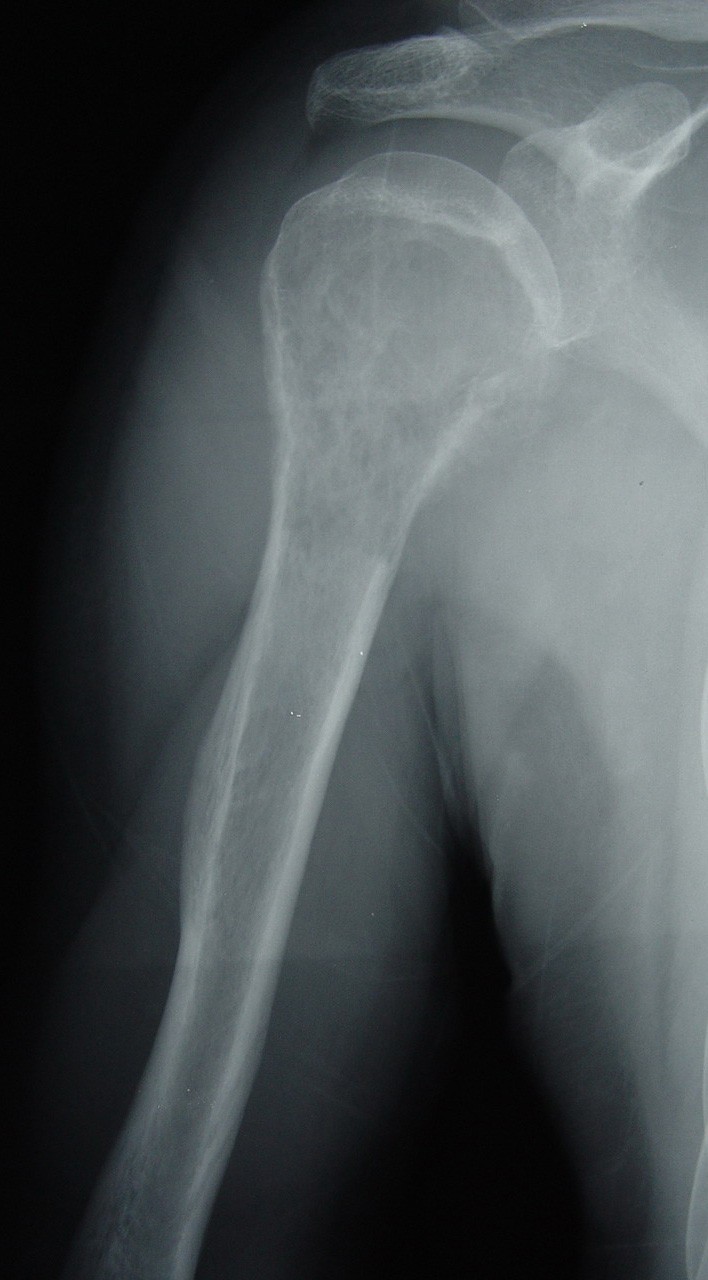

Preoperative Xray (AP view) of a 39year male patient with left Pain In Humerus After Breast Cancer It often affects people with breast, lung. In some cases, however, bone metastases cause little. The main symptoms of breast cancer that has spread to bone are: Bone metastasis is when cancer spreads to your bones from another part of your body. At first glance, shoulders seem distant from breasts and there is no immediately obvious connection. For patients with. Pain In Humerus After Breast Cancer.